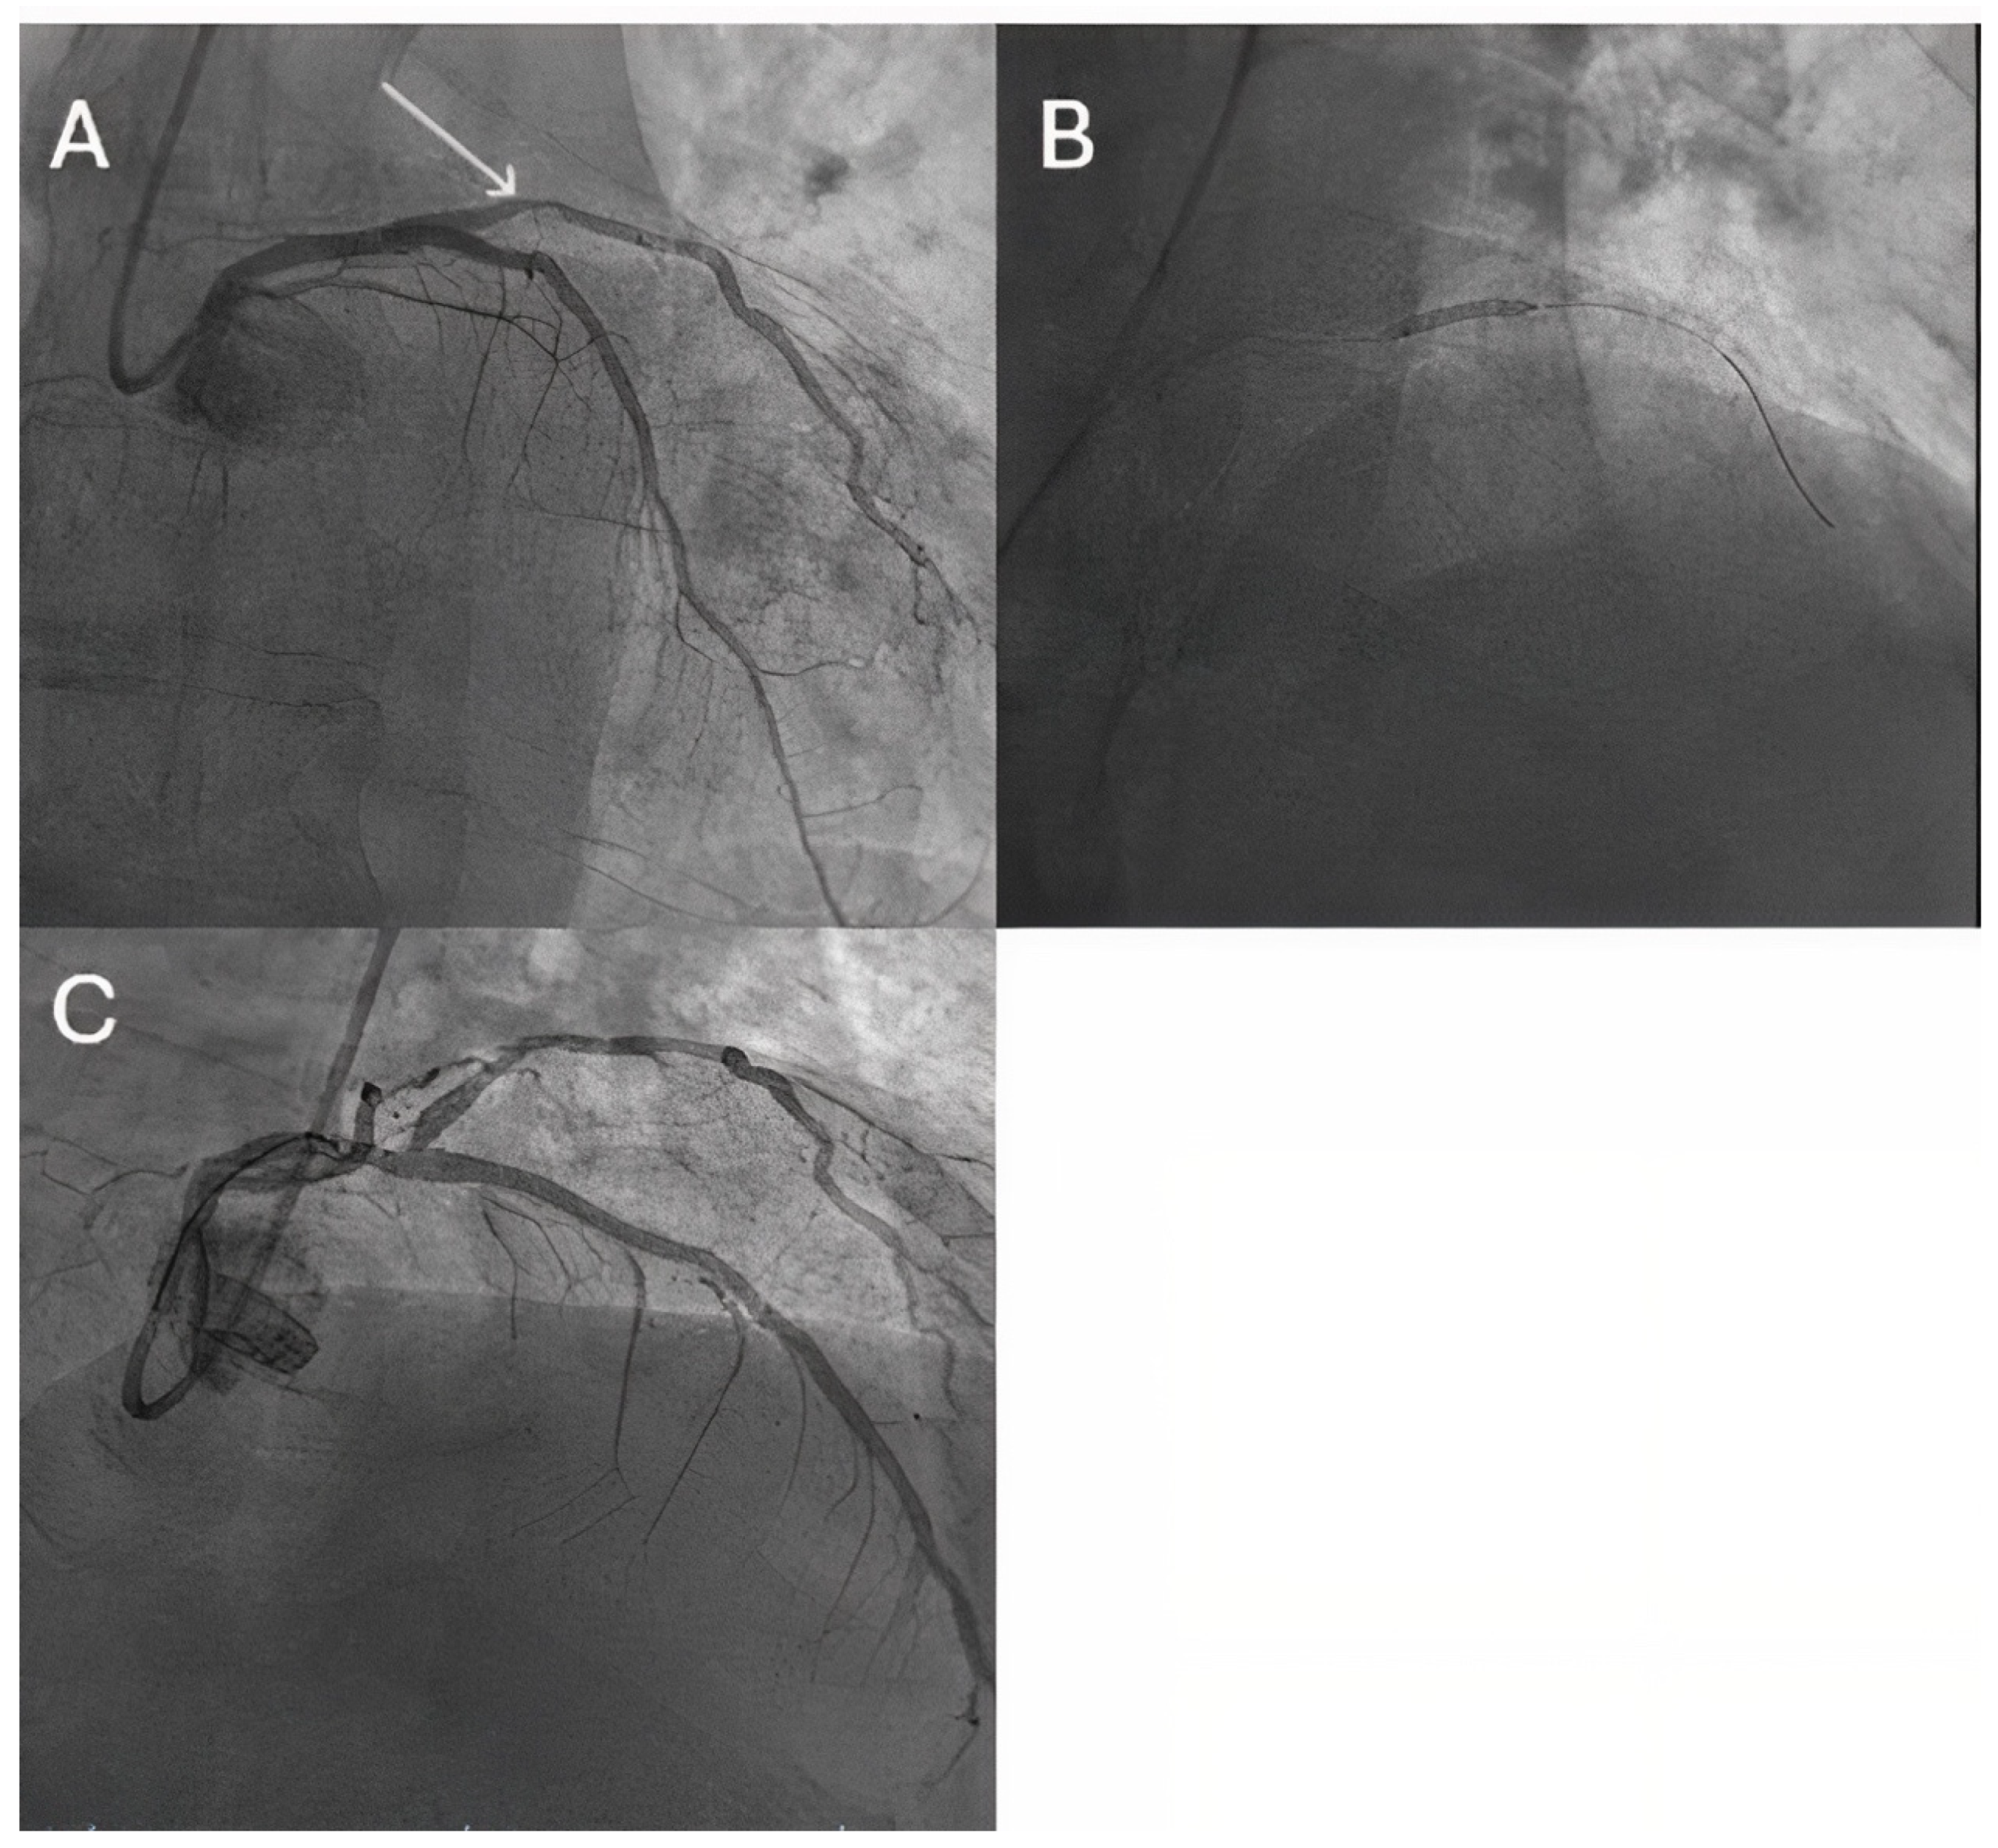

- Erdoğan, E.; Li, Z.; Zhu, Y.X.; Tufaro, V.; Feng, S.L.; Li, Q.; Liang, L.; Chang, S.; Bu, L.T.; Liu, B.; et al. DCB combined with provisional DES implantation in the treatment of De Novo Medina 0,1,0 or 0,0,1 left main coronary bifurcation lesions: A proof-of-concept study. Anatol. J. Cardiol. 2022, 26, 218–225. [Google Scholar] [CrossRef] [PubMed]

- Liu, H.; Tao, H.; Han, X.; Lu, Y.; Xue, X.; Feng, R.; Lv, F.; Liu, Y.; Jin, H.; Li, L.; et al. Improved Outcomes of Combined Main Branch Stenting and Side Branch Drug-Coated Balloon versus Two-Stent Strategy in Patients with Left Main Bifurcation Lesions. J. Interv. Cardiol. 2022, 2022, 8250057. [Google Scholar] [CrossRef] [PubMed]

- Pan, L.; Lu, W.; Han, Z.; Pan, S.; Wang, X.; Shan, Y.; Peng, M.; Qin, X.; Sun, G.; Zhang, P.; et al. Drug-coated balloon in the treatment of coronary left main true bifurcation lesion: A patient-level propensity-matched analysis. Front. Cardiovasc. Med. 2022, 9, 1028007. [Google Scholar] [CrossRef]